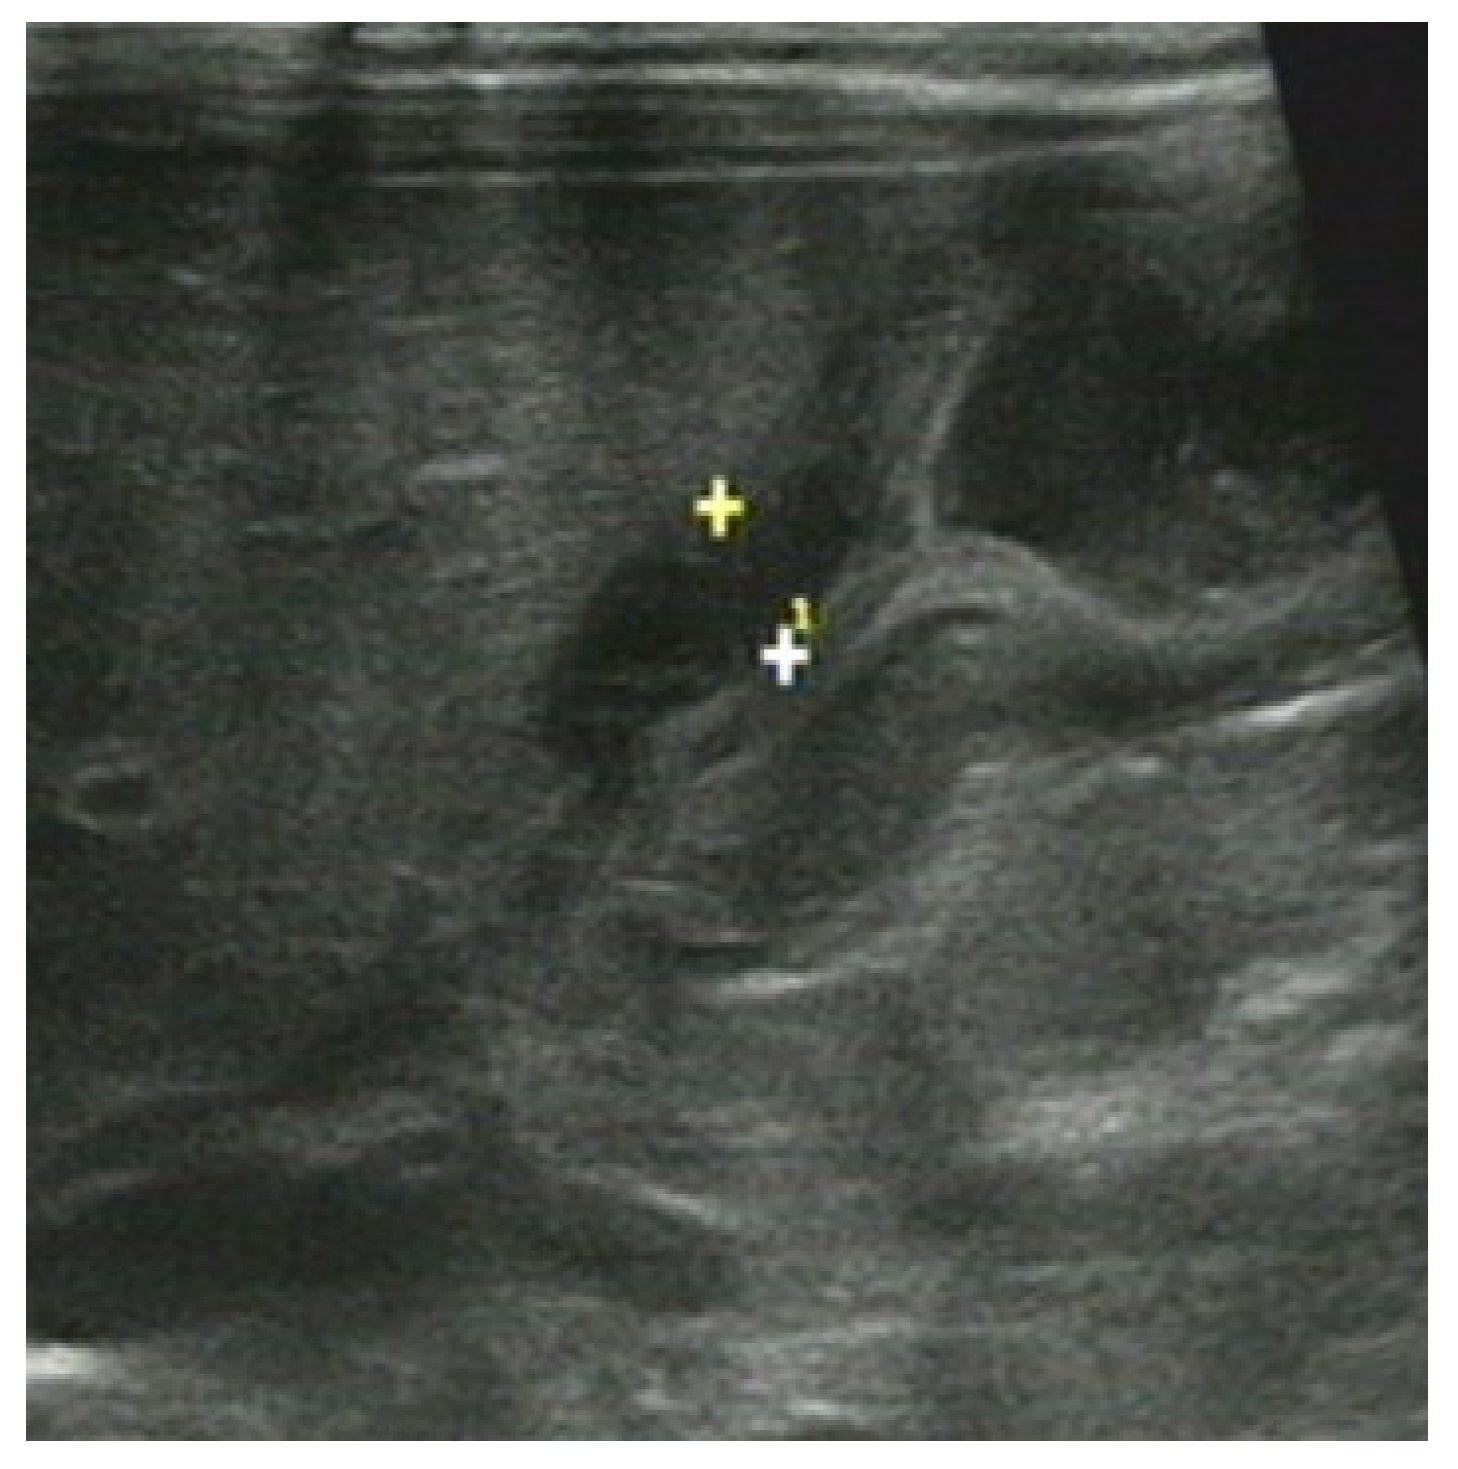

3.2. The Ultrasonic Manifestations

3.2.1. The Ultrasonic Signs of Intestinal Obstruction

3.2.2. The Corresponding Ultrasound Findings of Diseases Leading to Neonatal Ileus